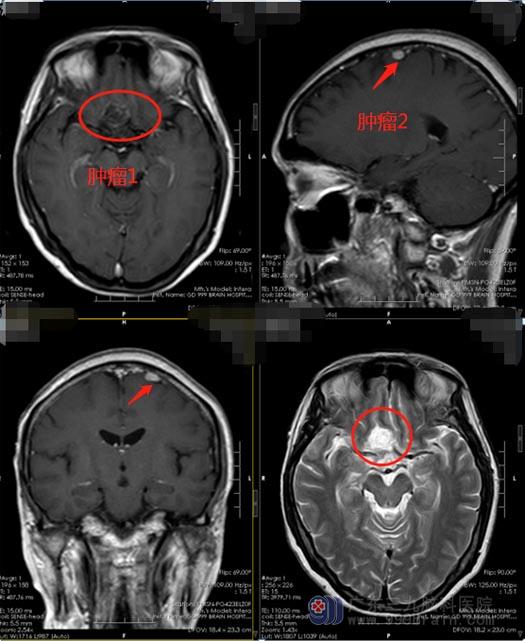

2周前,杨阿姨在当地医院体检,头部影像检查提示右侧额叶底部结节,考虑脑膜瘤或血管瘤,阿姨及家人一下子紧张起来。在广东三九脑科医院进一步头颅核磁共振检查发现:1.前颅窝底占位,考虑脑膜瘤;2.左侧额部占位,考虑小脑膜瘤。

医院副院长、神经外五科主任鲁明考虑到,周阿姨颅内有不同部位的两个肿瘤,并且挤压视神经及右侧大脑前动脉,和血管关系也很密切;手术切除是最有效的治疗方法,因肿瘤与视路、垂体、下丘脑、海绵窦、颈内动脉及其分支关系紧密,手术全切除难度较大。家属了解手术风险后,经过充分考虑,同意手术治疗。鲁明带领手术团队从右侧翼点入路行右侧额底鞍旁脑膜瘤切除,再定位左侧额部,将左侧额部的脑膜瘤一并完整切除。手术非常成功,杨阿姨术后恢复很好,未出现术后并发症。